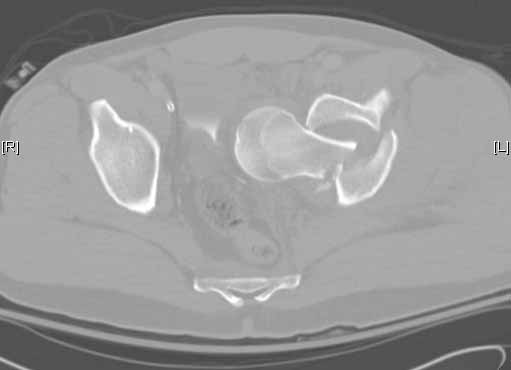

Subject: Intrapelvic fracture dislocation of the hip

Anyone ever seen one like this before? Any suggestions on how to get that thing out of there, because I tried and couldn't -got called in to the OR by a colleague with the patient already on the fracture table and 2 big incisions ( lateral and iliac crest) already made.  Gave up after an hour or two and will try again if I can figure the solution.